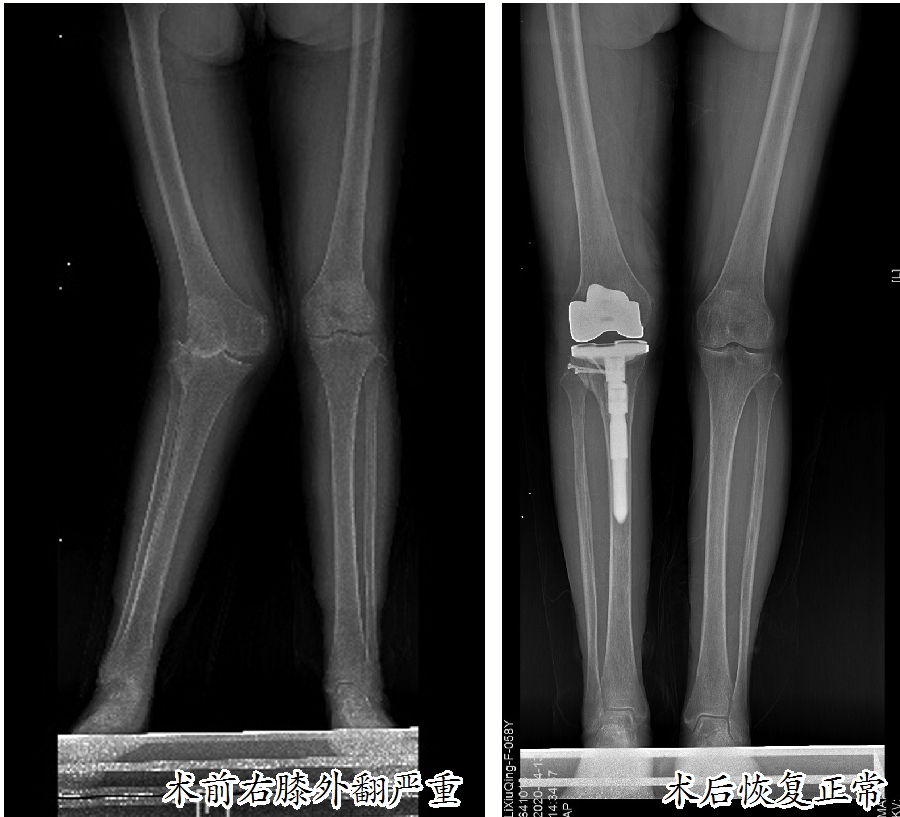

这名患者名叫李素严(化名),患有类风湿性关节炎多年,近半年感觉双侧膝关节疼痛严重,影响了日常生活,来到市人民医院骨科中心关节外科、运动医学科就诊。入院后,经过双侧膝关节X线检查发现:双膝关节存在不同程度的退行性变,其中右膝关节退化严重,重度外翻畸形,外翻角度超过30度,属于重度膝外翻,已经到了必须治疗的地步。

膝外翻又称为“X型腿”“K型腿”或“碰膝症”。在医学上,正常人的膝关节有5至7度的外翻角,如果超过此角度就是病态。膝关节向外侧倾斜10至15度为轻度外翻,超过15至30度为中度外翻,外翻角大于30度为重度外翻。